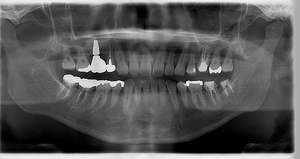

インプラント治療の症例3

レントゲン写真

- Befor

- After

| 年齢 | 50代・男性 |

|---|---|

| 主訴 | 左下7番 |

| 治療内容 | 右下7番インプラント埋入 |

| 治療費 | 合計:572,000円 診断料:55,000円 埋入料:165,000円 サージカルガイド:55,000円 静脈内鎮静麻酔:77,000円 仮歯:55,000円 上部構造(フルジルコニア):165,000円 (2023年1月現在) |

| 治療期間 | 約8ヶ月 |

| リスク・副作用 | リスク・副作用 |

| 治療方針 | 骨が十分にあるため、骨造成をすることなく埋入した。かみ合わせが強いので、負荷がかからないよう、夜寝るときにマウスピースをつけるよう指示をした。 |

| 担当者所見 | 左下6番7番のインプラントは他院で埋入しており、右下7番は抜歯したままで、かみ合わせの歯が落ちてきてしまうのでインプラントを埋入しました。 |